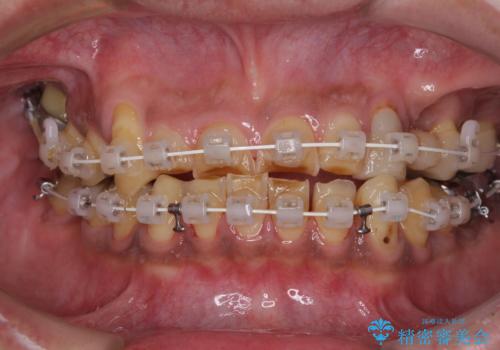

- 矯正装置

- 審美装置

矯正治療は想定通り長期化しましたが、しっかりと奥歯の咬み合わせを向上させて前歯の被蓋を改善させることができました。